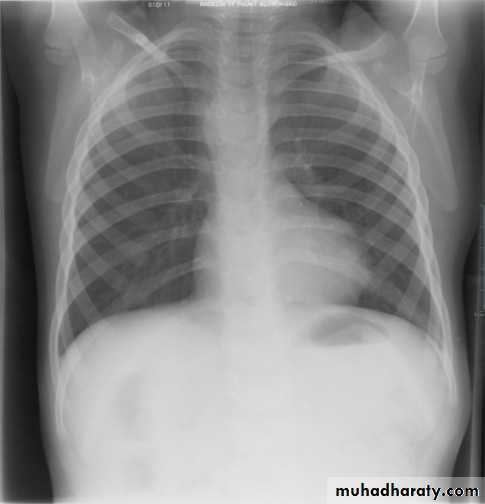

Normal thymus gland ( sail shape sign )